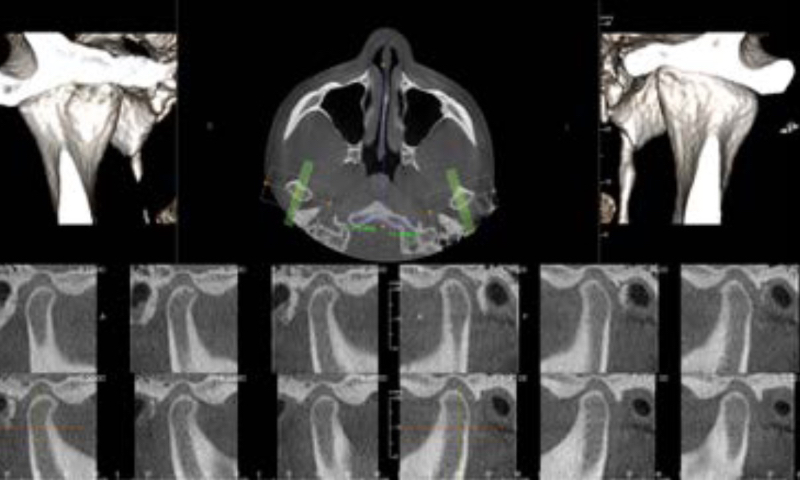

全周囲からの情報を得られる360°スキャニング

全周囲からの情報を得るために 360度回転して撮影します。撮影中の回転角度を大きくすると、情報量が多くなり、画像データが補正できます。

パノラマ撮影機をベースにしたCT撮影機は、その構造上200度前後の回転しかできない機種が多く、メタルアーチファクトを抑えることができません。

東京都港区青山の歯医者 360°スキャンで金属アーチファクトの発生が少ない。

360°スキャンで金属アーチファクトの発生が少ない。

エックス線の水平入射

エックス線を水平に入射することで、エックス線の散乱を最小限にします。

金属アーチファクトを最小化し、関心部位への陰影障害を極小にします。

東京都港区青山の歯医者 画質の向上はもちろん、よりエックス線を抑えた撮影が実現。

画質の向上はもちろん、よりエックス線を抑えた撮影が実現。